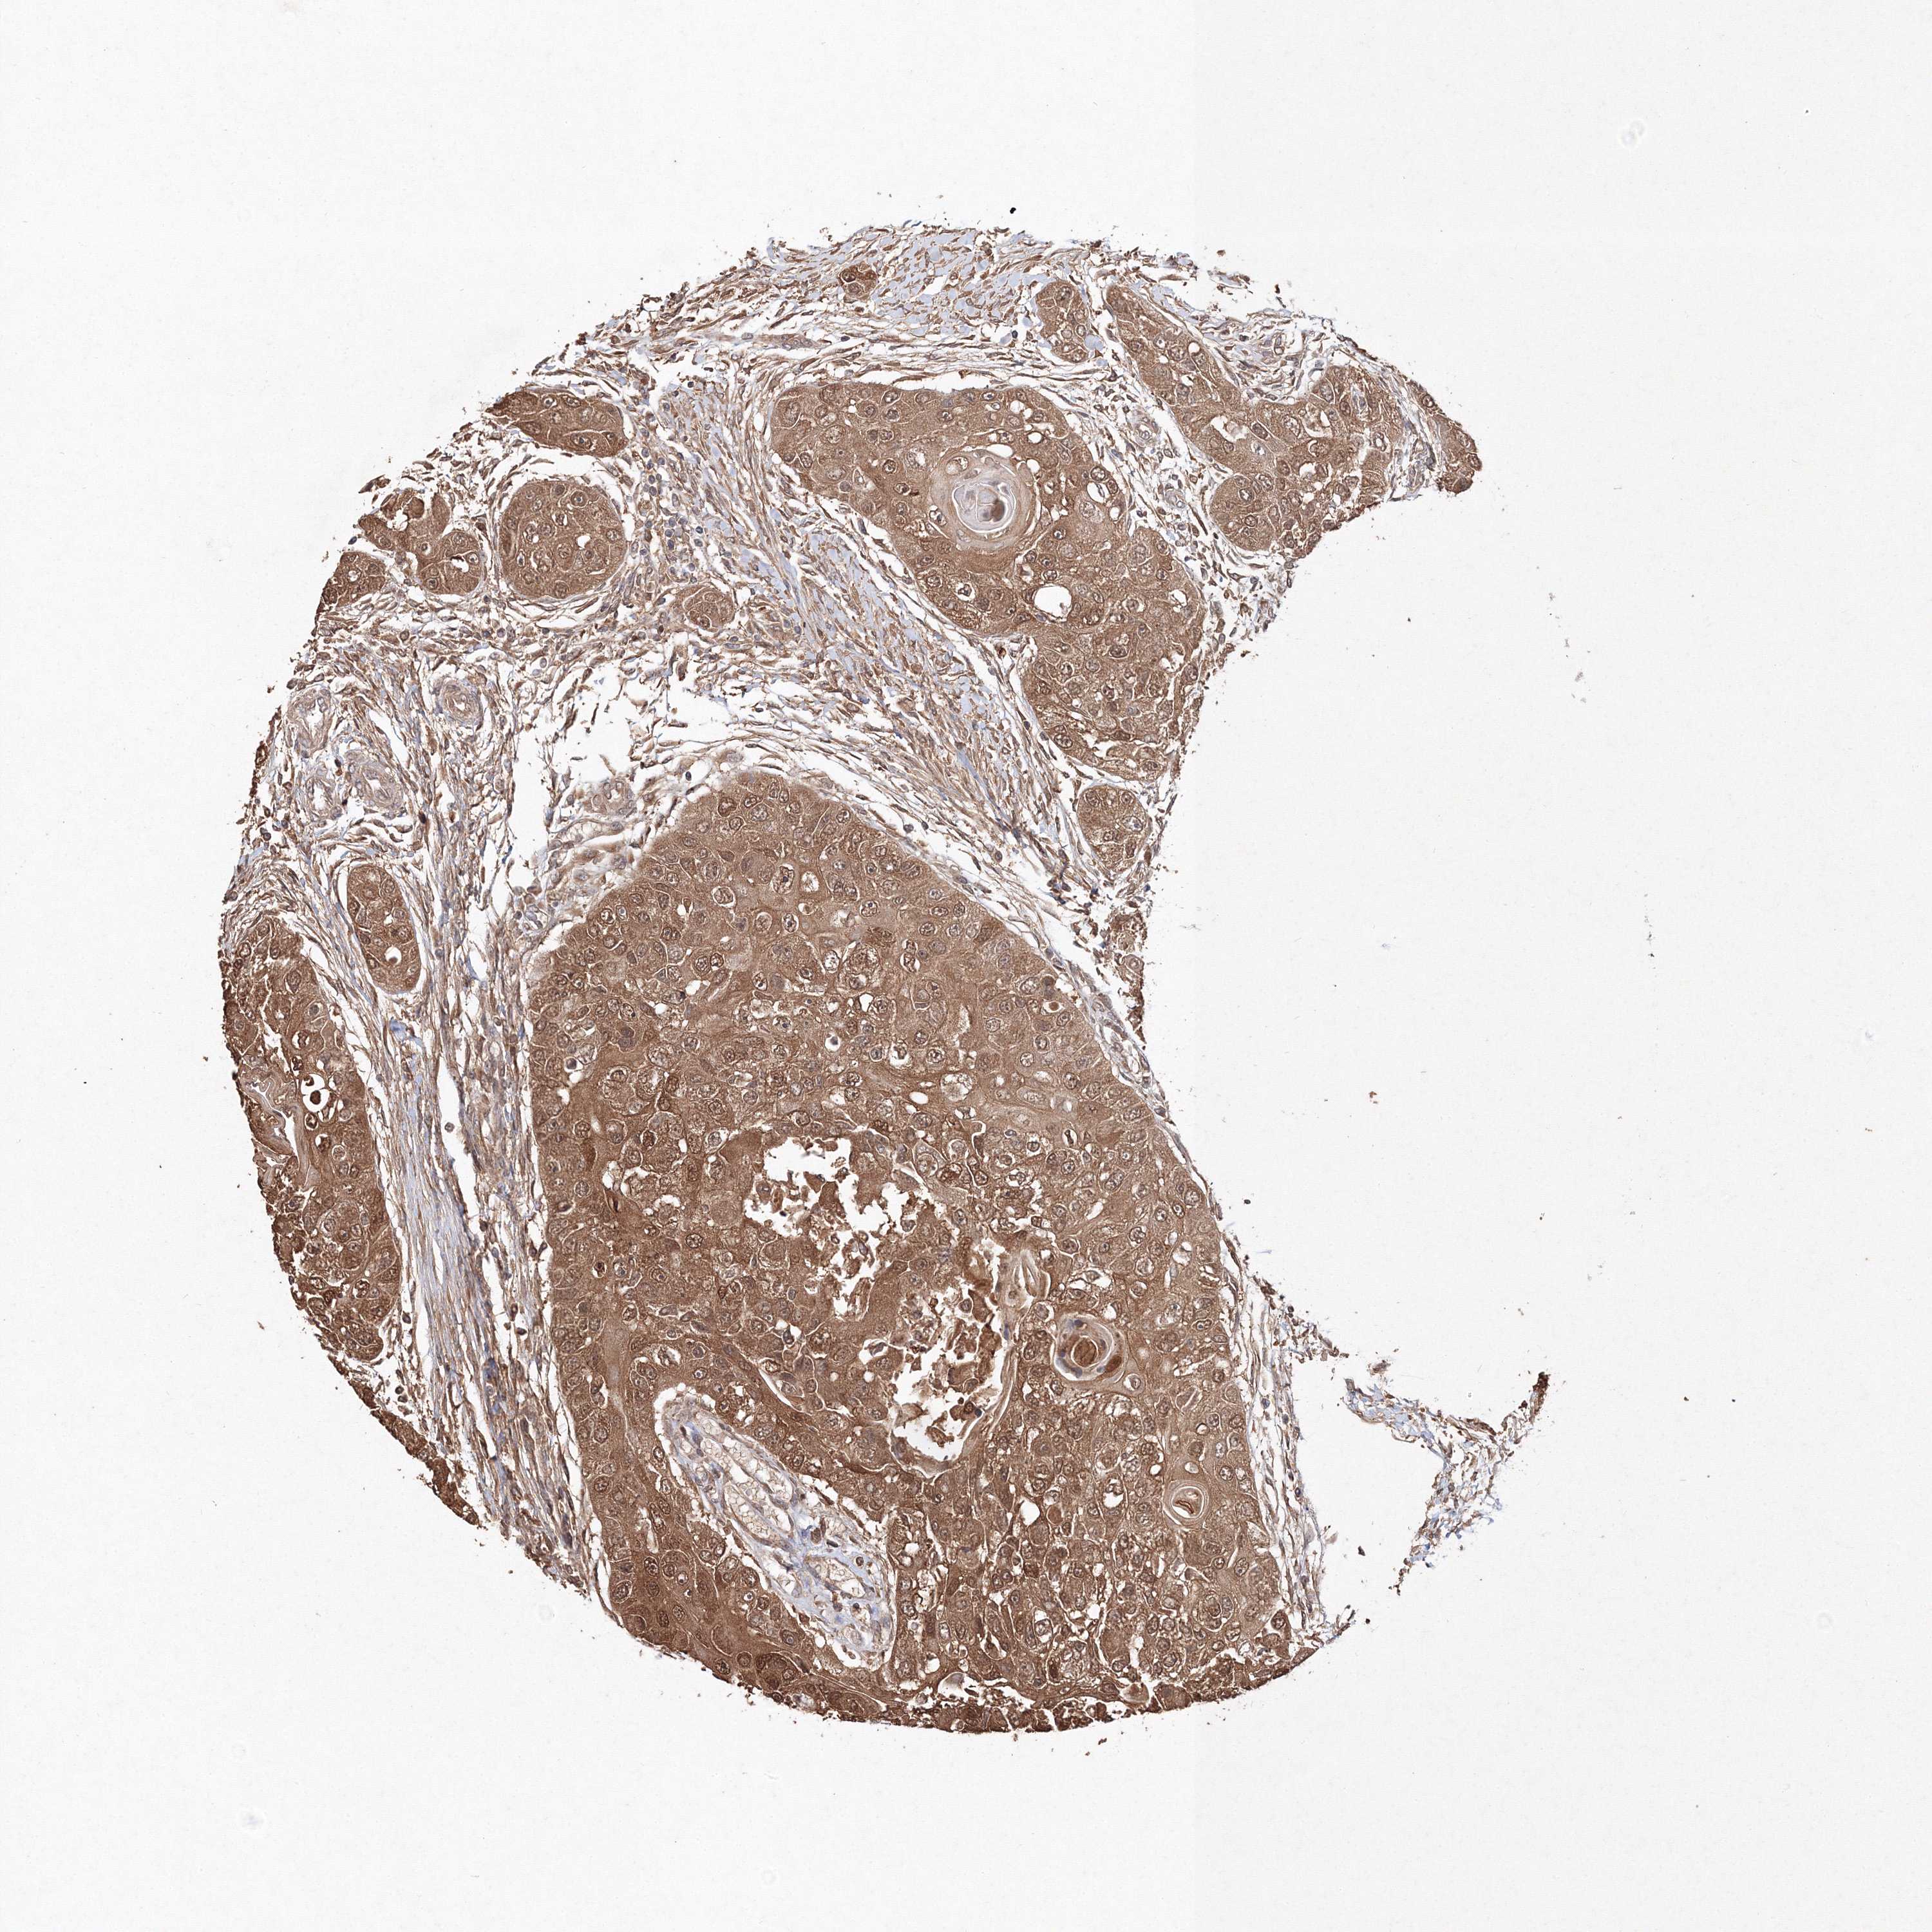

HEAD AND NECK CANCER - Protein expressioni

A mouse-over function shows sample information and annotation data. Click on an image to view it in a full screen mode. Samples can be filtered based on level of antibody staining by selecting one or several of the following categories: high, medium, low and not detected. The assay and annotation is described here.

Antibody stainingi

Antibody staining in the annotated cell types in the current human tissue is reported as not detected, low, medium, or high, based on conventional immunohistochemistry profiling in selected tissues. This score is based on the combination of the staining intensity and fraction of stained cells.

Each image is clickable and will lead to virtual microscopy that enables deeper exploration of all samples and also displays staining intensity scores, fraction scores and subcellular localization as well as patient and tissue information for each sample.

Antibody CAB034320

Squamous cell carcinoma, NOS

Squamous cell carcinoma, metastatic, NOS